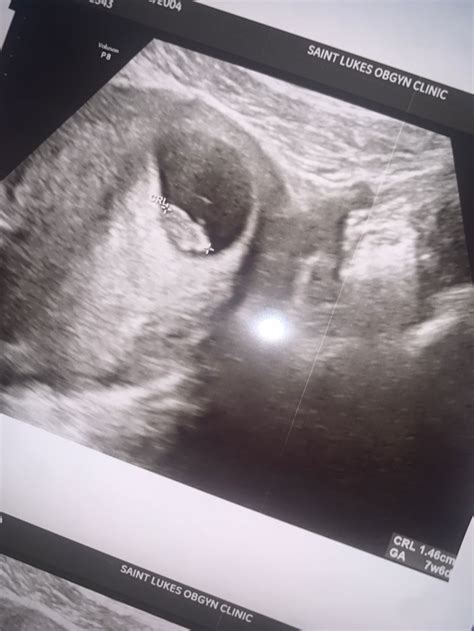

An 8 week sonogram is an ultrasound examination performed around the eighth week of pregnancy. This non-invasive procedure uses high-frequency sound waves to create images of the fetus and the uterus. The primary goal of an 8 week sonogram is to confirm the pregnancy, determine the gestational age, and assess the fetus’s development.

• Determining Gestational Age: Measuring the crown-rump length (CRL) of the fetus helps determine the exact gestational age, which is essential for monitoring the pregnancy’s progress.

The results of an 8 week sonogram are interpreted by a trained ultrasound technician and reviewed by an obstetrician. Key findings include:

• Gestational Age: The CRL measurement helps determine the exact gestational age, which is crucial for monitoring the pregnancy’s progress.

• Fetal Heartbeat: The presence of a heartbeat is a positive sign of a viable pregnancy.